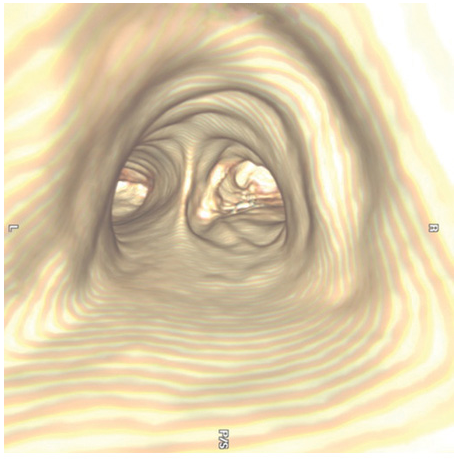

Recent advances in computer processing have allowed the development of helical CT scanning. Helical CT technology results in faster scans with improved contrast enhancement and thinner collimation. The image is obtained during a single breath-holding maneuver that allows less motion artifact. In addition, helical CT scanning allows the collection of continuous data over a larger volume of lung than is possible with conventional CT. Data from the imaging procedure can be reconstructed as images in planes other than the traditional cross-sectional (axial) view, including coronal, or sagittal planes (Fig. C-3A). Finally, sophisticated volumetric “3D” representations of structures can be produced (Fig. C-3B) including the ability to perform a virtual bronchoscopy, mimicking direct visualization through a bronchoscope (Fig. C-4).

Virtual Bronchoscopy

The three-dimensional (3D) image of the thorax obtained by MDCT can be digitally stored, reanalyzed, and displayed as 3D reconstructions of the airways down to the sixth- to seventh-generation. Using these computed generated reconstructions, a “virtual” bronchoscopy can be performed (Fig. C-5). Virtual bronchoscopy has been proposed as an adjunct to conventional bronchoscopy in several clinical situations: It can allow accurate assessment of the extent and length of an airway stenosis, including the airway distal to the narrowing; it can provide useful information about the relationship of the airway abnormality to adjacent mediastinal structures; and it allows preprocedure planning for therapeutic bronchoscopy to help ensure the appropriate equipment is available for the procedure. Virtual bronchoscopy can also be used to perform noninvasive follow-up of patients with treated airway lesions. Navigational systems using virtual bronchoscopy have been developed to allow pathfinding to guide the bronchoscopist to a peripheral region within the lung, allowing peripheral lung lesions to be sampled more efficiently. Finally, with the advent of endobronchial lung volume reduction surgery in the management of pulmonary emphysema, virtual bronchoscopy may be able to help target the area of peripheral lung for endobronchial valve procedures. The extent of emphysema in each segmental region together with other anatomic details may help in choosing the most appropriate subsegments. However, software packages for the generation of virtual bronchoscopic images are relatively early in development and their utilization and potential impact on patient care are still unknown. In addition to allowing virtual bronchoscopy, advances in computing capabilities and digital imaging allow the bronchoscopic images obtained through a real bronchoscopic examination to be stored as digital images and reviewed after completion of the procedure.